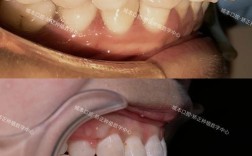

牙龈组织异常

牙龈的健康状态和生物学特性是影响牙龈位置的关键,正畸过程中,若患者口腔卫生维护不当,可能引发牙龈炎、牙周炎,导致牙龈增生或退缩,托槽、弓丝等矫治器周围若清洁不彻底,易堆积菌斑,刺激牙龈组织增生,使牙龈缘肿胀、肥厚,微笑时显得“牙龈过多”,部分患者牙龈本身较薄,牙槽骨吸收后牙龈易随牙齿移动而退缩,但这种情况相对少见,更多见于正畸后牙龈退缩导致的“黑三角”而非露龈笑。